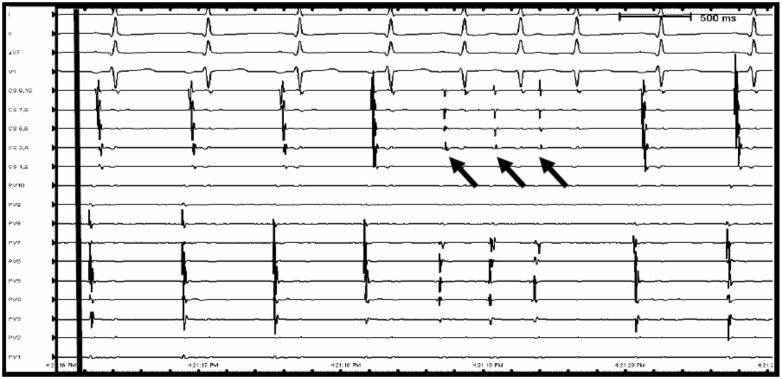

After obtaining consent, the patient was brought to the electrophysiology (EP) lab, where tachycardia could not be induced with programmed electrical stimulation. Activation mapping was performed using the Biosense-Carto™ system (Biosense Webster, Diamond Bar, CA, USA). By having the patient periodically swallow 10–20 cm3 of saline, non-sustained atrial tachycardia was induced (Figure 2). The Lasso catheter (Biosense Webster) was used to take multiple simultaneous activation points from a single premature atrial contraction. The earliest activity was localized to the anterior aspect of the right superior pulmonary vein (RSPV). After radiofrequency isolation of the RSPV and ablation of the right anterior ganglionated plexus, the tachycardia was non-inducible despite repeated swallowing and isoproterenol medication. The patient remained asymptomatic, without any further palpitations, in the 12 months of follow-up after the ablation.

Figure 2.

Surface and intracardiac electrograms of swallowing-induced arrhythmia. Top 4 leads (I, II, aVF, and V1) reflect surface electrocardiogram tracings. CS 1–10 and PV1–10 reflect intracardiac electrograms originating from coronary sinus and right superior pulmonary vein, respectively. The patient is in normal sinus rhythm until swallowing water (longitudinal black line), followed by three beats of non-sustained atrial tachycardia (black arrows) with earliest activation in the Lasso catheter located in the right superior pulmonary vein. CS, coronary sinus; PV, pulmonary vein.